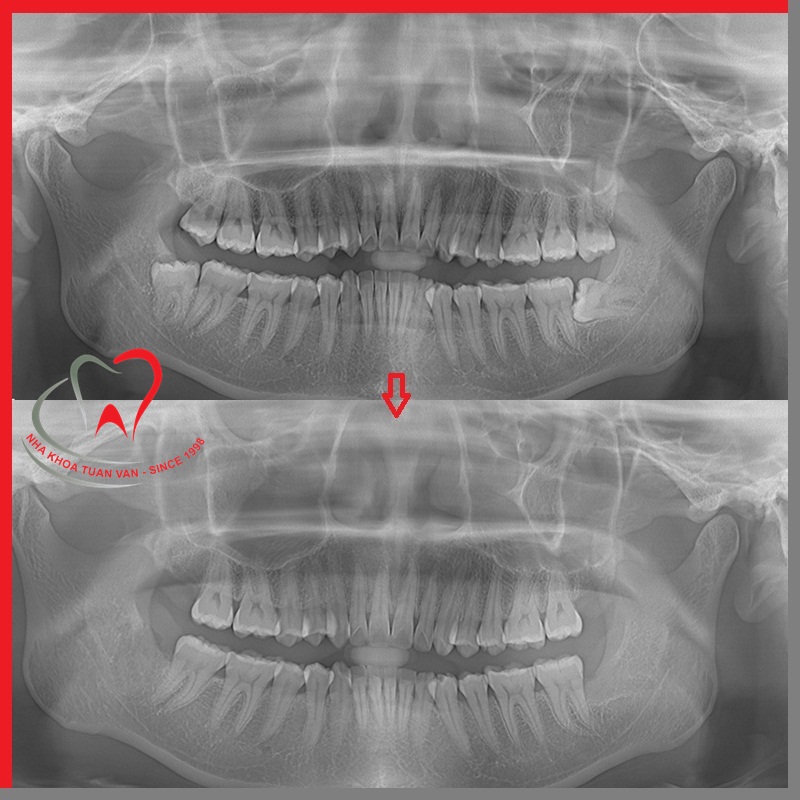

Bước 2: Chụp X-Quang

Để xác định một cách chính xác nhất tình trạng răng mọc ngầm, mọc lệch, xác định độ phức tạp của ca nhổ để đưa ra những phương án xử lý phù hợp.

.jpg)

Trước và sau khi nhổ răng khôn tại Nha khoa Tuấn Vân